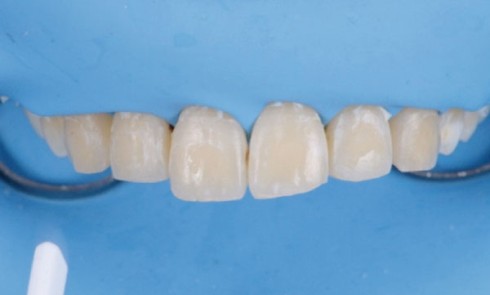

Article réservé à nos abonnés Traitement des leucomes apparus lors des thérapeutiques orthodontiques fixes

Bien que les dispositifs multi-attaches constituent actuellement une entrave à l’hygiène bucco-dentaire beaucoup moins importante que par le passé, ils...